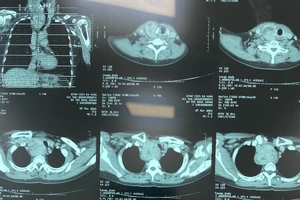

Phẫu thuật lấy bướu giáp 'khủng' trốn trong lồng ngực 10 năm

Ngủ ngồi suốt 2 năm vì mang bướu cổ nặng 0,5 kg